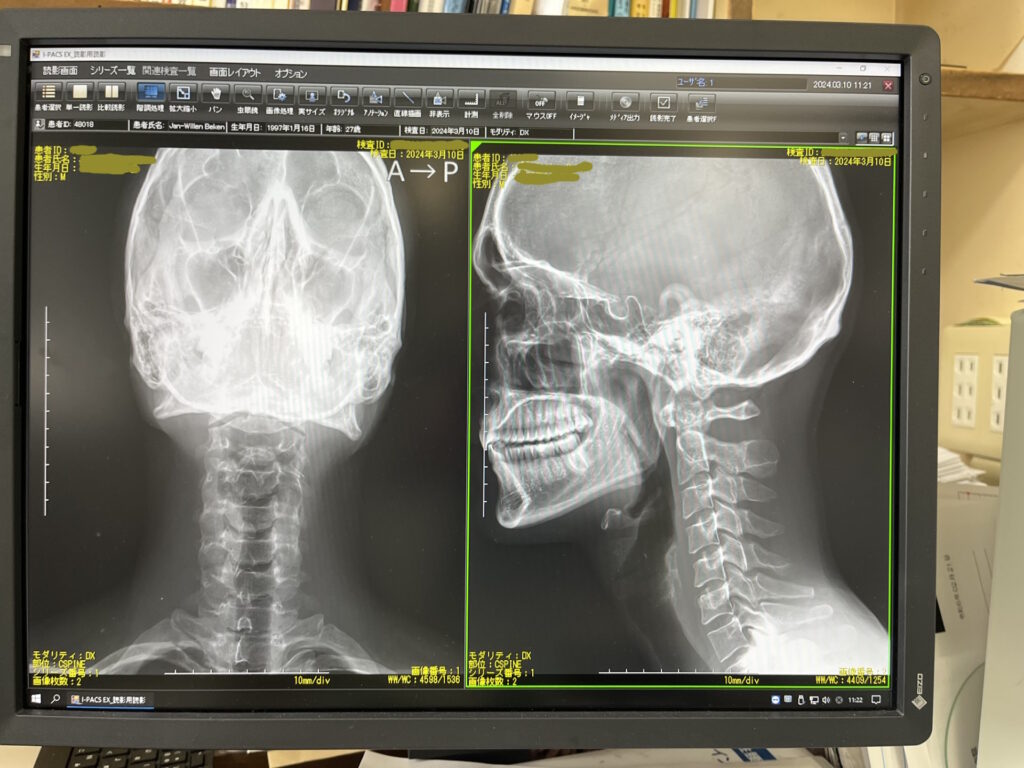

Later, sitting in the hospital waiting for an X-ray, I kept replaying the moment in my head. Trying to understand what had really happened.

Right after the crash, I already knew it was serious. My neck wouldn’t move. For weeks, I could barely turn my head.